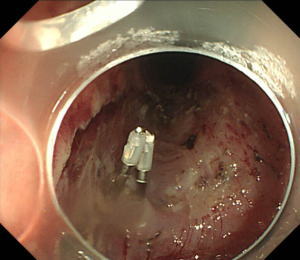

| 【胃ESD】 |

粘膜下層剥離術が終了したところ。大きな合併症はなく終了しました。 |

最大径50mm程度のやや大きめの早期胃癌でしたが治癒切除されていました。 |